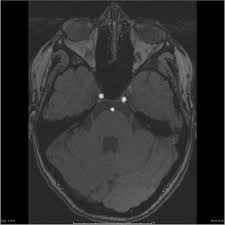

Carotid Cave Aneurysm Coiled And Mca Fenestration Carotid Cave Aneursyms Have A Complex Relationship To The Du Aneurysm Subarachnoid Hemorrhage Fenestration